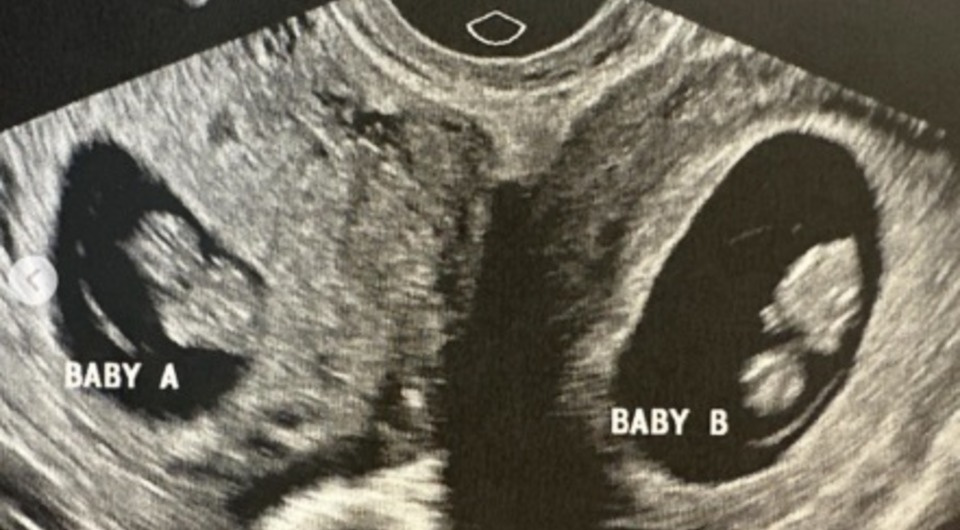

Врачи обнаружили, что 32-летняя жительница Алабамы с двумя матками вынашивает ребенка в каждой из них. Как отмечает Science Alert со ссылкой на AFP, такие беременности очень редки — один случай на 50 миллионов. Судя по всему, две яйцеклетки были оплодотворены независимо друг от друга. Сейчас роды протекают нормально, поэтому женщина надеется, что к концу года ей удастся родить естественным путем. Однако высока вероятность, что ей все-таки понадобится кесарево сечение.